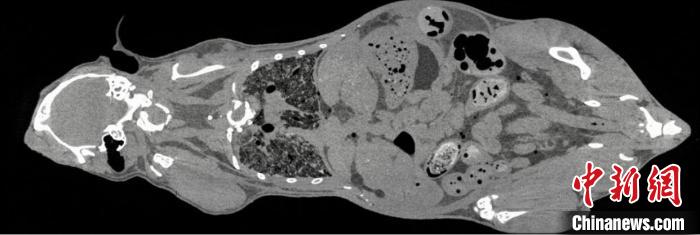

鼠全身成像。 中科院高能所 供圖